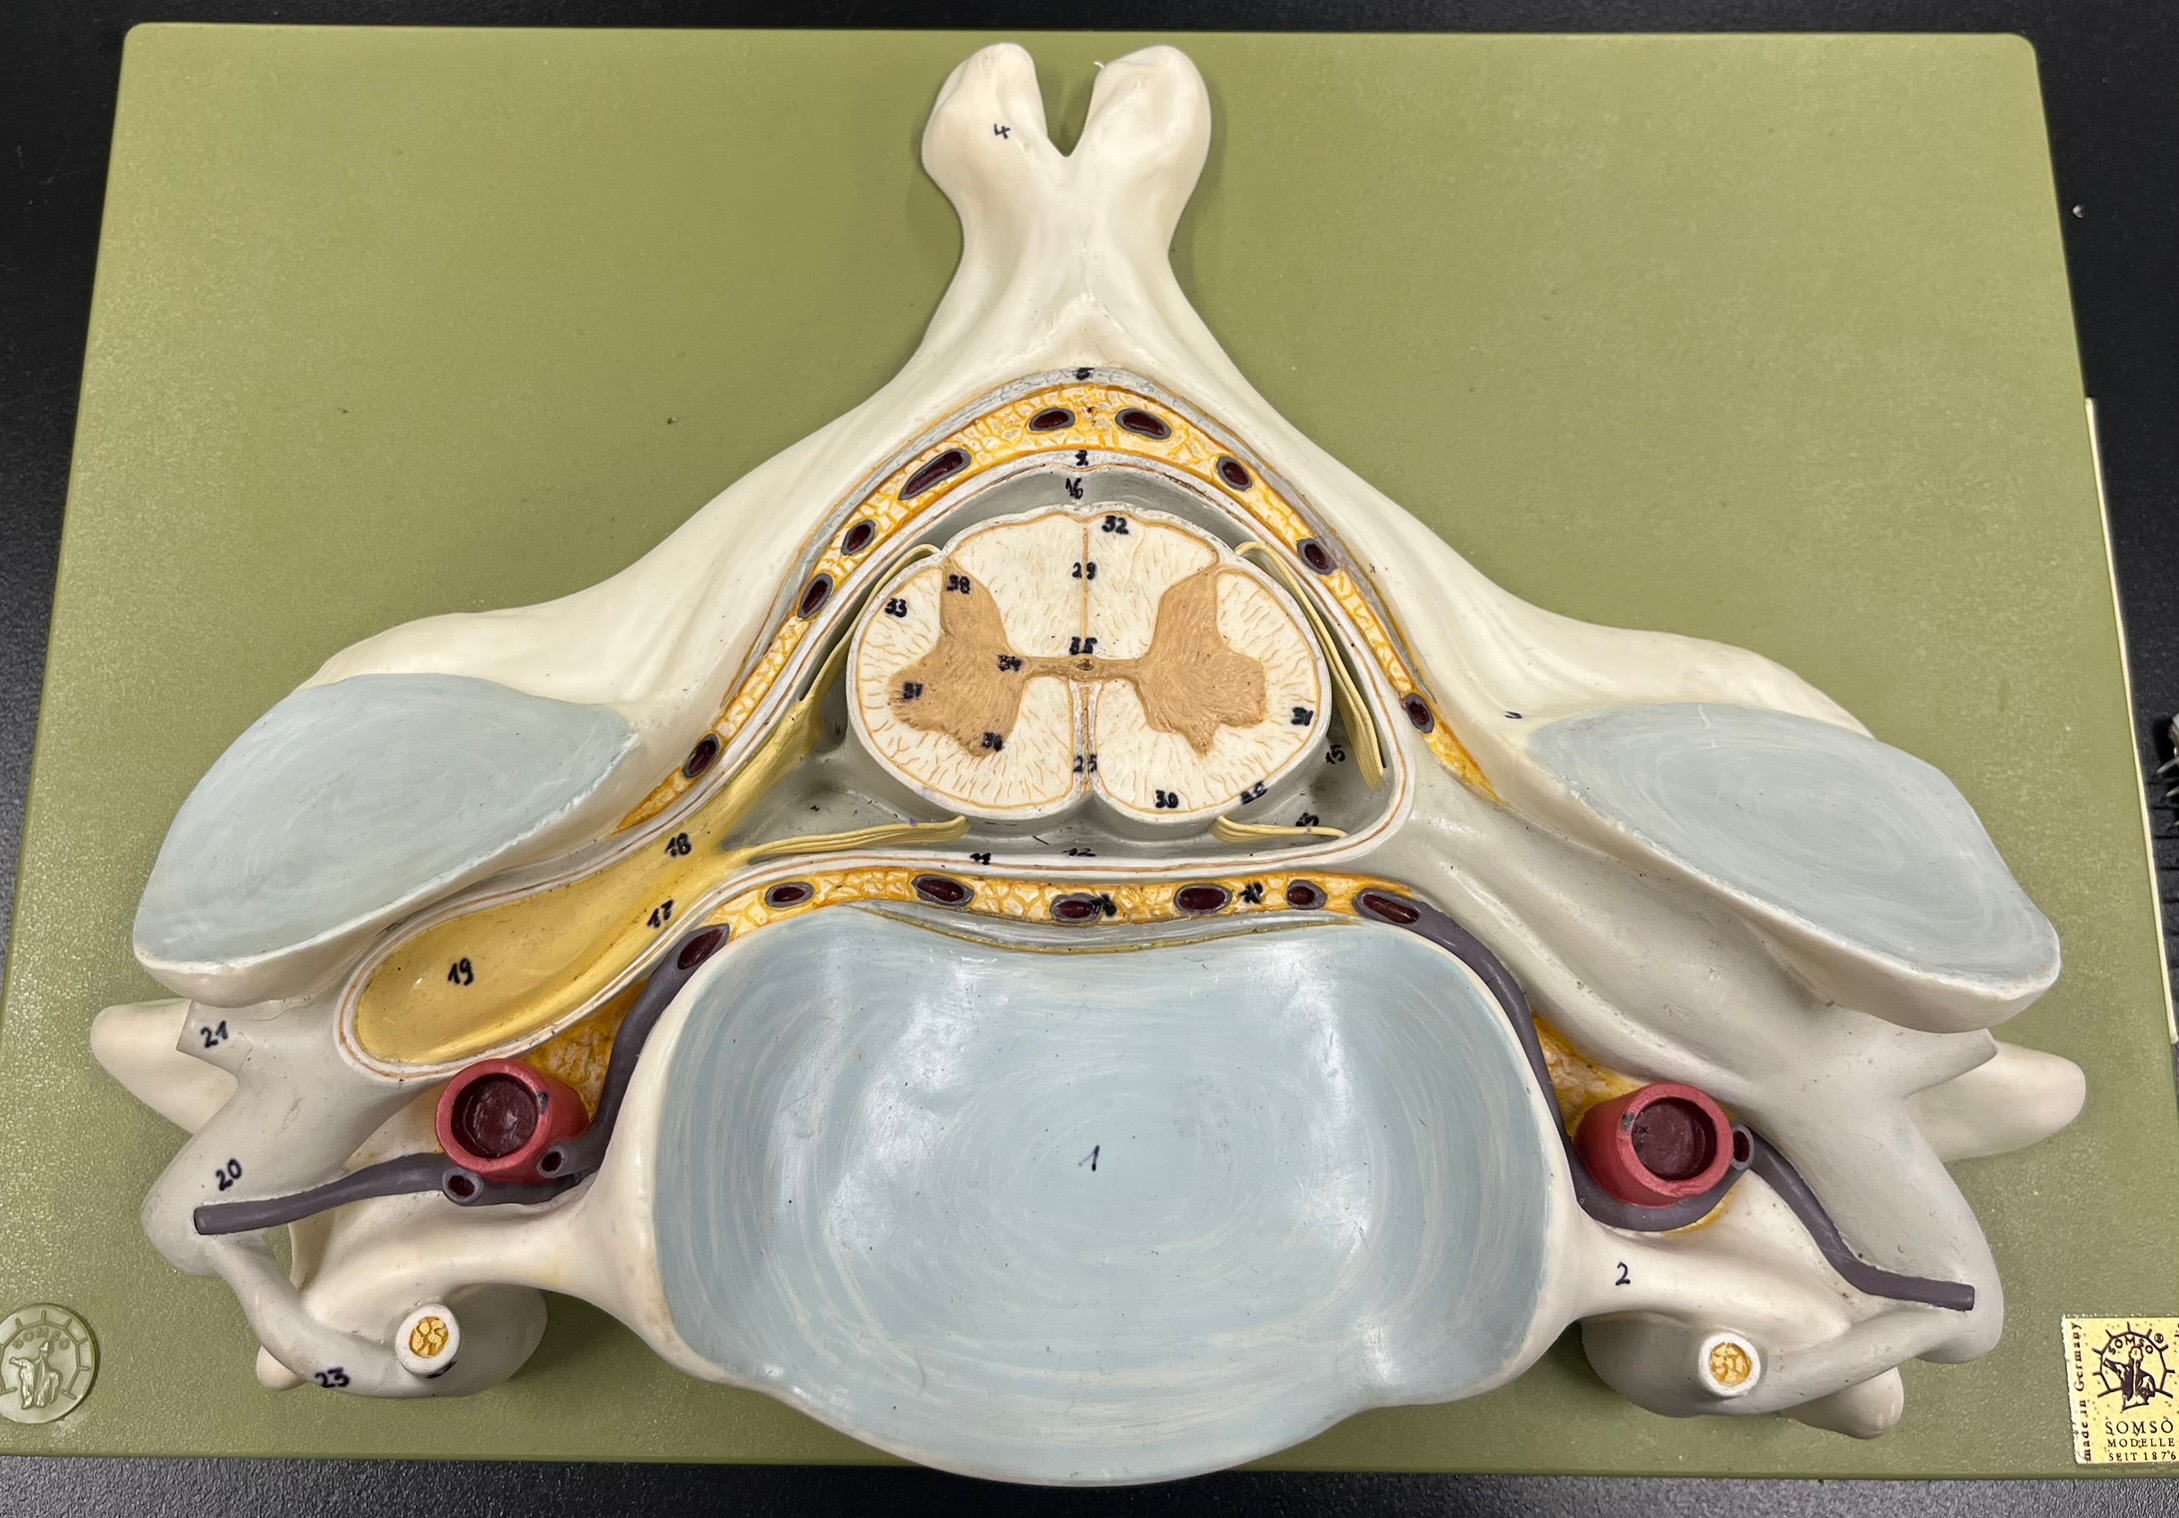

epidural space

dura mater

subdural space

arachnoid mater

subarachnoid space

pia mater

denticulate ligaments

What is the groove here?

anterior median fissure

posterior median sulcus

posterior (dorsal) horn

posterior (dorsal) horn; R—>L

anterior (ventral) horn

lateral horn (selected models)

gray commissure

central canal

anterior column

lateral column

posterior column

white commissure

posterior (dorsal) root ganglion

What is the bulb here?

posterior (dorsal) root ganglion

posterior (dorsal) root

posterior (dorsal) root

anterior (ventral) root

anterior (ventral) root

dorsal ramus

dorsal ramus

ventral ramus

ventral ramus

rami communicantes

rami communicantes

sympathetic chain ganglia

sympathetic chain ganglia